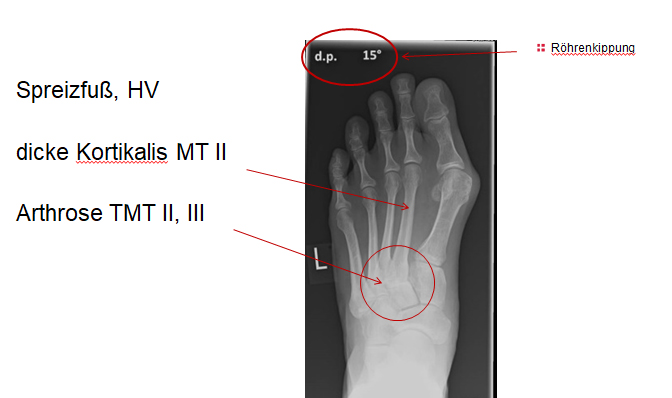

Bei nicht traumatischen Arthrosen am Tarsometatarsale (TMT) II und III Gelenk handelt es sich meist um proximale Überlastungsschäden bei ausgeprägtem Spreizfuß mit Instabilität im TMT I Gelenk oder auch alleiniger Hypermobilität im TMT I und dadurch fehlender Lastaufnahme über den ersten Strahl.

Der ausgeprägte Spreizfuß führt bei vielen Patienten zu einer verringerten Lastübernahme am ersten Strahl. Ursache sind das medialisierte Os metatarsale I, sowie eine Hypermobilität im TMT I Gelenk. Unter Belastung weicht das Metarasale I nicht nur nach medial sondern auch nach dorsal aus, was die Belastung der Ossa metatarsalia II und III erhöht. Das typische klinische Symptom ist eine Transfer­metatarsalgie. Diese kann bereits bei einer isolierten Hypermobilität im TMT I auftreten. Sobald es zu einer isolierten Elevation des ersten Strahles unter Belastung kommt, steigt die Beanspruchung der medialen Metatarsalia. Weniger häufig sind posttraumatische Arthrosen, die nach Frakturen an den Basen der Metatarsalia oder (Sub-) Luxationen in der Lisfranc-Gelenklinie entstehen.

Die Überbelastung im Schaftbereich wird selten von den Patienten wahrgenommen. Manchmal findet sich vor allem am Os metatarsale II proximal eine Stressfraktur. Adaptiert sich der Knochen, kann im Röntgenbild häufig eine Kortikalisverdickung im Bereich der Metatarsale II und III Schäfte als Ausdruck einer vermehrten Lasteinleitung beobachtet werden (Abb. 4).

Eine Röntgenaufnahme unter Belastung mit Abbildungen des ganzen Fußes a. p. (mit 15-20° Röhrenkippung) und seitlich, sowie Schrägaufnahmen, reichen meist zur Diagnose. Manchmal ist ein MRT und DVT ergänzend hilfreich. Selten wird die Indikation für ein SPECT CT gestellt (Abb. 6).